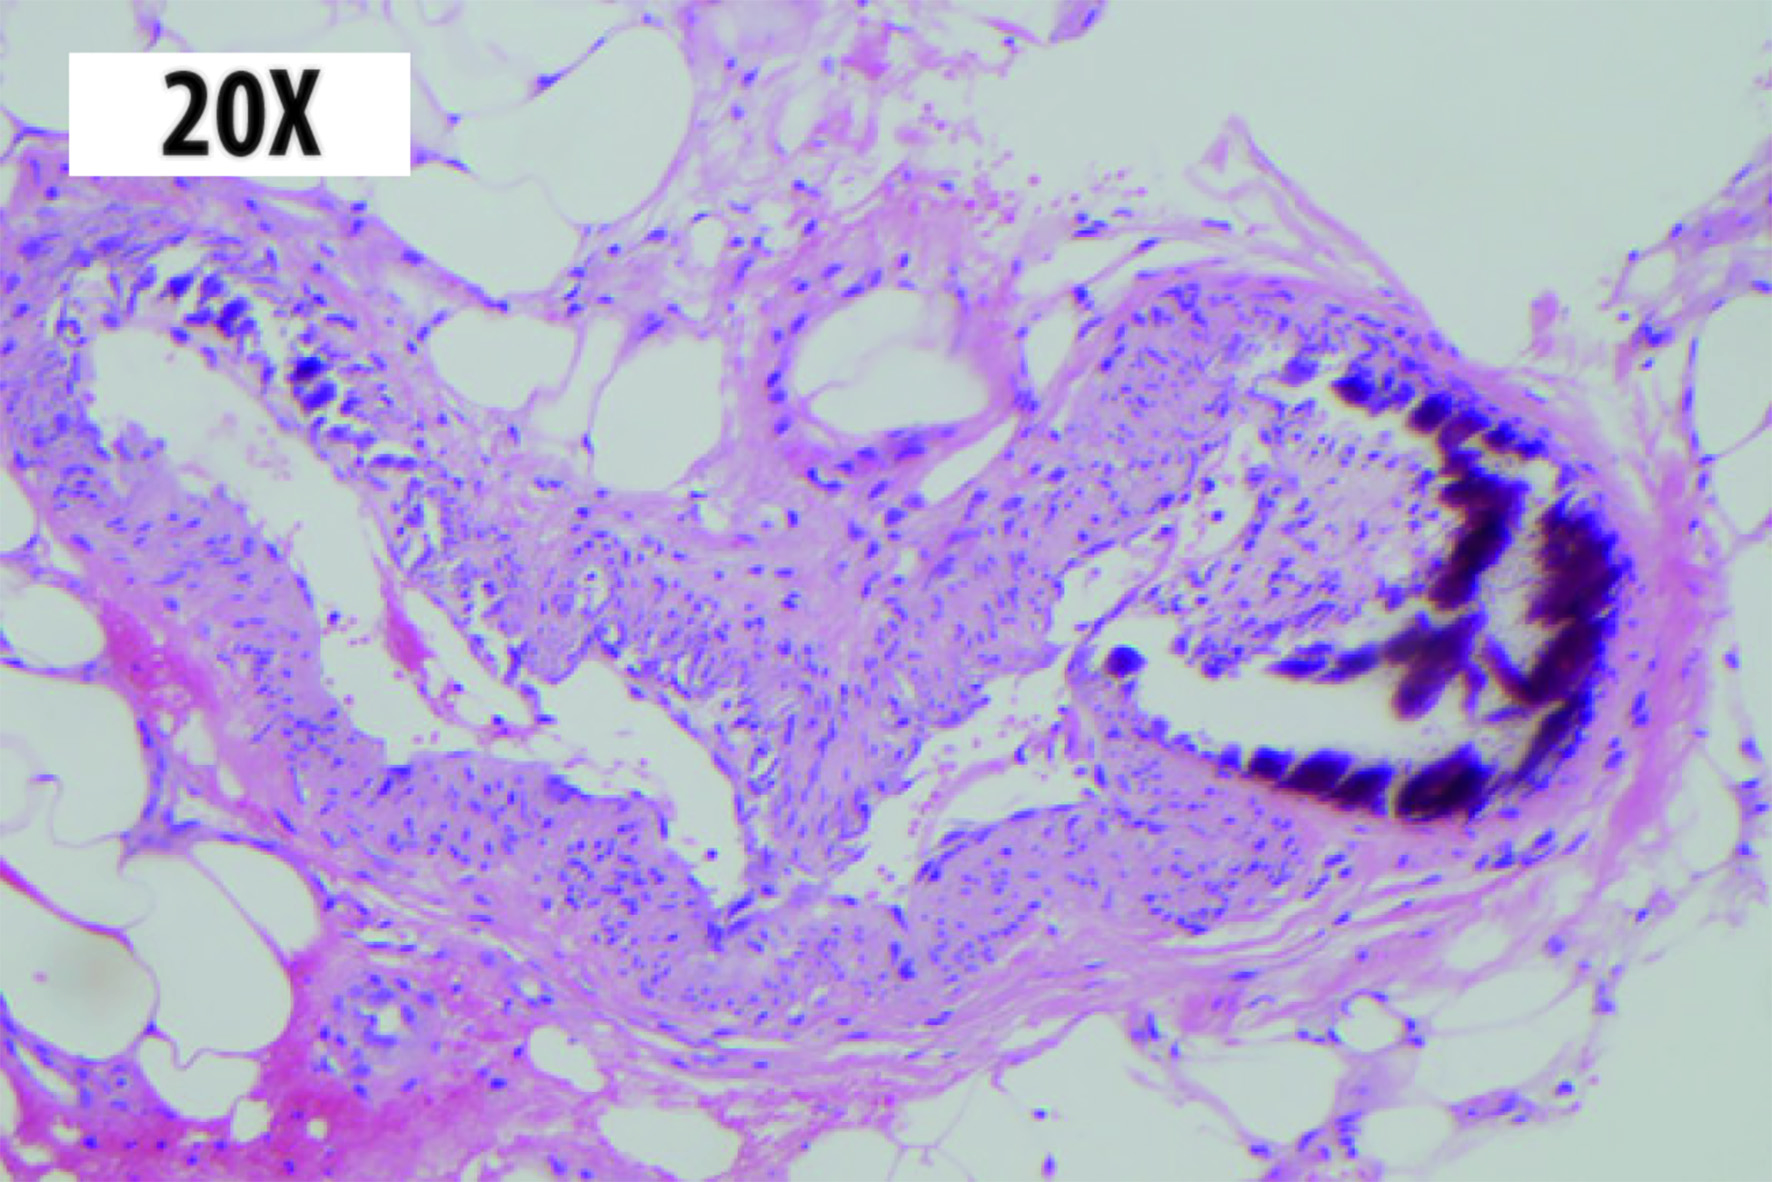

Dermatology Service was interconsulted, and a skin biopsy was performed obtaining anatomopathological findings compatible with calciphylaxis (Fig. 2).

Figure 2 Skin biopsy: hematoxylin-eosin stain 20x. Dystrophic calcification in medium size arteries with intimal proliferation is observed at the hypodermis level.